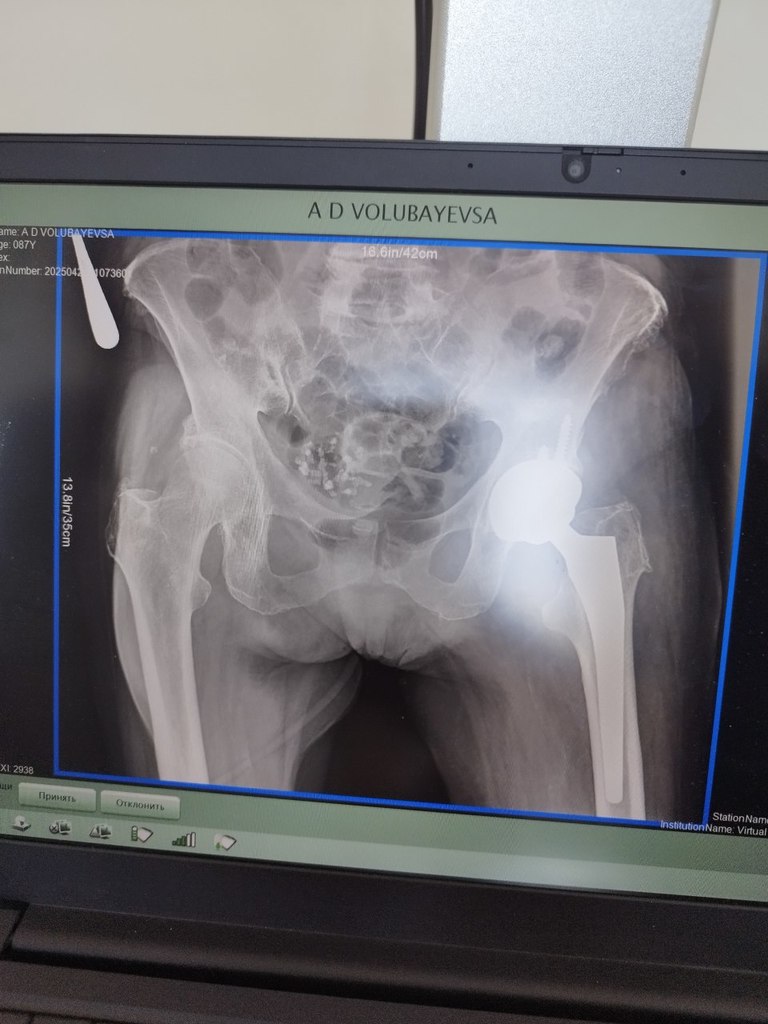

Сегодня снимок делали, дай Бог, завтра домой заберуIMG_20250421_175223_826.jpg.9cc654d3adcca6bddad793d7930ee6aa.jpg

Сегодня снимок делали, дай Бог, завтра домой заберу

Интересно, чашку бесцемнтную поставили..:icon_eek:

вижу ренген    снимок - эндо протез на левой стороне

не вижу ВЫВИХА о котором вы пишете